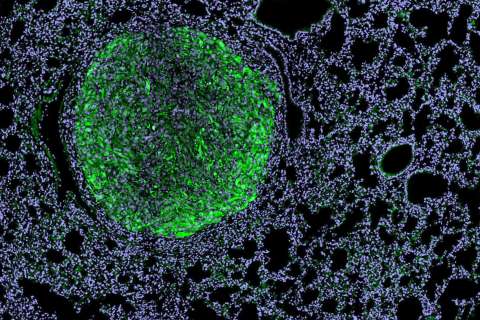

Dr. Arnold Chin's Laboratory is dedicated to improving the lives of patients with urologic malignancies. Much of their initial studies have focused on understanding the molecular pathways that program the tumor infiltrating lymphocytes in bladder and prostate cancer, which they have shown can influence tumor growth, ability to metastasize and response to immune-based therapies. More recently, they began studying the characteristics and drivers of bladder cancer stem cells.

Chin's laboratory currently studies two main areas:

1. They have identified an alternatively spliced form of a transcription factor, FOXP3, that activates and makes bladder cancer stem cells more aggressive. They will exploit this observation by understanding its basic biology and develop novel inhibitors of FOXP3.

2. They are characterizing the tumor population in micrometastatic lymph nodes, which they hypothesize is enriched in a cancer stem cell population. Identifying this population will improve pathologic staging as well provide therapeutic insight into inhibiting the process of metastases.